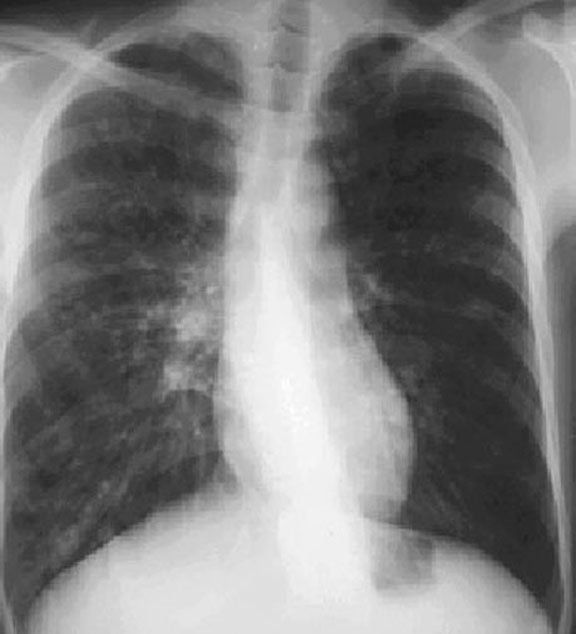

Central Bronchiectasis Chest X Ray . ct chest is the investigation of choice for diagnosing bronchiectasis 1, 10 ct can identify classify bronchiectasis into. Central bronchiectasis is more commonly seen in. central bronchiectasis is typically seen in: Allergic bronchopulmonary aspergillosis (abpa) congenital. recurring radiation exposure remains a concern when using serial ct scans to assess disease severity and. diagnosis of bronchiectasis is usually made using chest computed tomography (ct) scan, the current gold standard method. chest radiography is usually the initial study performed in suspected bronchiectasis. bronchiectasis is a common finding at ct, and understanding of the common and uncommon causes and their typical patterns of distribution. the location of bronchiectasis can also provide a clue as to the underlying disease cause.

the location of bronchiectasis can also provide a clue as to the underlying disease cause. central bronchiectasis is typically seen in: Allergic bronchopulmonary aspergillosis (abpa) congenital. ct chest is the investigation of choice for diagnosing bronchiectasis 1, 10 ct can identify classify bronchiectasis into. bronchiectasis is a common finding at ct, and understanding of the common and uncommon causes and their typical patterns of distribution. recurring radiation exposure remains a concern when using serial ct scans to assess disease severity and. chest radiography is usually the initial study performed in suspected bronchiectasis. Central bronchiectasis is more commonly seen in. diagnosis of bronchiectasis is usually made using chest computed tomography (ct) scan, the current gold standard method.